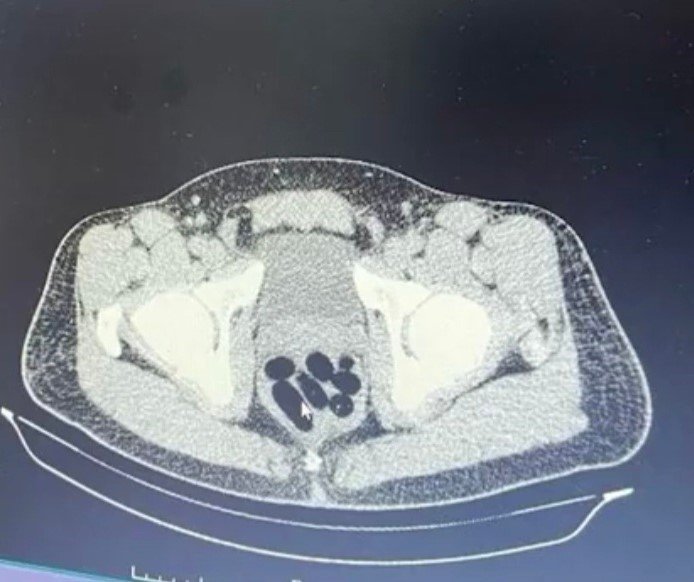

Kayseri İl Emniyet Müdürlüğü Narkotik Suçlarla Mücadele Şube Müdürlüğü ekipleri, uyuşturucu madde ticareti yapan şahıslara yönelik analiz çalışması yürüttü. M.R.B'nin (23) kente uyuşturucu madde getireceğini tespit eden ekipler operasyon düzenledi. Gözaltına alınan şahsın hastanedeki iç beden muayenesinde 77 adet kapsül şeklinde 1 kilo 134 gram narkotik madde ele geçirildi. Şahsın midesindeki maddeler cerrahi müdahale ile çıkarılırken, şahıs hakkında "uyuşturucu madde ticareti yapmak" suçundan adli işlem başlatıldı.